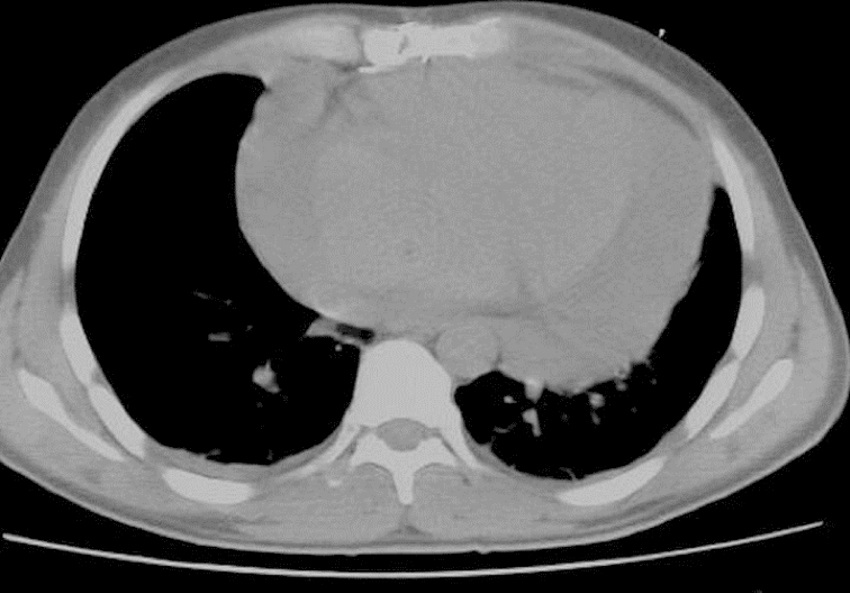

All patients were assessed by helical CT. In order to determine the entry point of PE drainage, 10 mm range images were taken from the heart apex to the arcus aorta. After the assessment, the skin was marked on the determined entry point (Figure 1). To ensure that the metallic needle was in the right place, CT was performed. And to prevent complications that could occur during electrocardiogram (ECG) monitoring, an intravenous saline with IV opening was inserted, and blood pressure was monitored at frequent intervals.

Having been colored and disinfected, the marked area was covered with sterile drapes. As a local anesthetic agent, 2% lidocaine was used. Then, an 18 G needle with negative puncture was entered to the pericardial cavity, the needle was fixed at the level of liquid aspiration, and the CT was taken again to reaffirm the needle's position (Figure 2). After confirming that it was in the intrapericardial space, the liquid was aspirated and evaluated. If hemorrhagic characteristics were thought to be possible after confirming that the blood defibrinated, a 0.035" guidewire was sent to the pericardial cavity through the needle (Figure 3). The needle was removed and the CT was taken; after confirming that the guidewire was in the intrapericardial cavity, an 8 or 10 F nephrostomy catheter was advanced into the pericardial cavity through a catheter guide. A three-way tap was installed in the tip of the catheter and the liquid was poured into a 50 ml syringe. The catheter was identified and it was connected to the closed underwater drainage system (Figure 4).